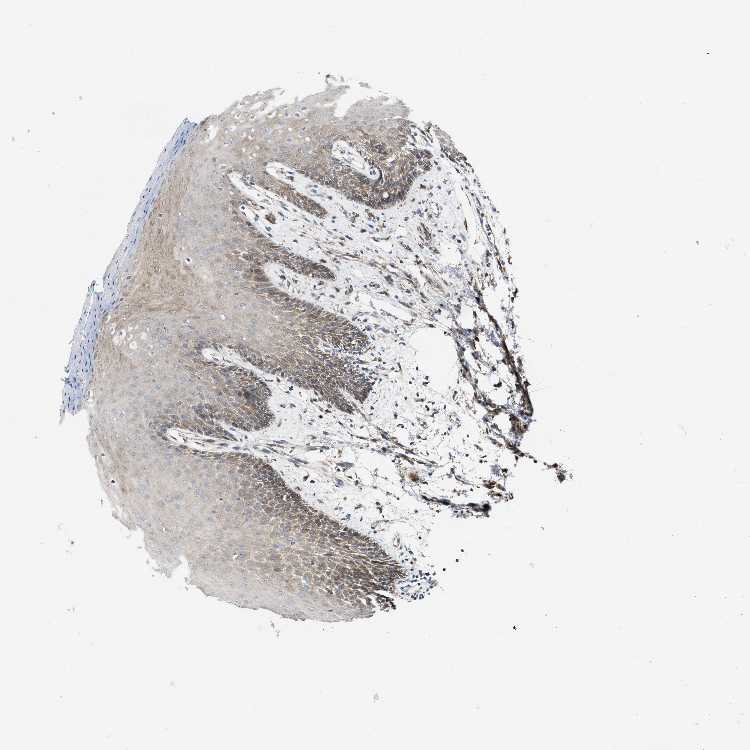

ORAL MUCOSA - Antibody stainingi

Antibody staining in the annotated cell types in the current human tissue is reported as not detected, low, medium, or high, based on conventional immunohistochemistry profiling in selected tissues. This score is based on the combination of the staining intensity and fraction of stained cells.

Each image is clickable and will lead to virtual microscopy that enables deeper exploration of all samples and also displays staining intensity scores, fraction scores and subcellular localization as well as patient and tissue information for each sample.

Antibody HPA002025Antibody CAB014894

Squamous epithelial cells LowMedium